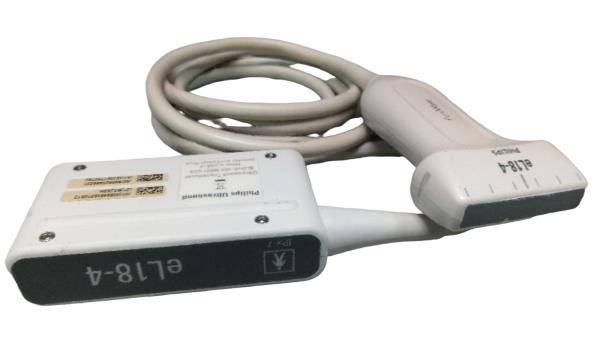

Linear(L40): L11-4Ds

- Application: Vascular, Small parts, Musculoskeletal, Carotid, Nerve, Orthopedic

- Number of element: 80

- Center frequency: 7.5MHz

- Working frequencies: 5 – 10MHz